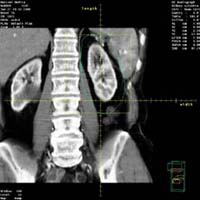

»ç±¸Ã¼ ÁúȯµéÀÇ

Áø´ÜÀº ¼Òº¯ ¹× Ç÷¾× »ýÈÇÐ °Ë»ç, Ç÷û

°Ë»ç, ½Å»ý°Ë µîÀ¸·Î ³»·ÁÁý´Ï´Ù. ¼Òº¯°Ë»ç»ó

Ç÷´¢¿Í ´Ü¹é´¢ À¯¹«¸¦ ¾Ë¾Æº¸°í, Ç÷¾×

»ýÈÇÐ °Ë»ç»ó ½Å±â´É ÁöÇ¥ÀÎ Å©·¹¾ÆÆ¼´Ñ°ú

Ç÷Áß ¿ä¼Ò Áú¼Ò, ±×¹Û¿¡ ÄÝ·¹½ºÅ×·Ñ, ¾ËºÎ¹Î

µîÀÇ ¼öÄ¡¸¦ Á¶»çÇÕ´Ï´Ù. Ç÷û °Ë»ç»ó

»ç±¸Ã¼½Å¿°ÀÇ °¡´ÉÇÑ ¿øÀÎÀÎ BÇü °£¿°°ú

CÇü °£¿° Ç¥½ÄÀÚ, È«¹Ý¼º ³¶Ã¢ÀÇ Ç×ÇÙÇ×ü,

Ç÷û º¸Ã¼ÀÇ °¨¼Ò µîÀ» Á¶»çÇÕ´Ï´Ù. ¸¶Áö¸·À¸·Î

½Å»ý°ËÀ¸·Î Á¤È®ÇÑ Áø´Ü¸íÀ» ¾òÀ¸¸é ±×

ÁúȯÀÇ ¿¹Èĸ¦ ÃßÁ¤ÇÒ ¼ö ÀÖÀ¸¸ç Ä¡·á¹ýÀÌ

Á¤ÇØÁý´Ï´Ù. ½Å»ý°ËÀº ½ÅÀåÀü¹®Àǰ¡ ½ÃÇàÇϹǷÎ

°ÅÀÇ ¾ÈÀüÇÏ¸ç ½ÅÀå¿¡´Â Ç÷°üÀÌ ¸¹À¸¹Ç·Î

ÀϺο¡¼ ÃâÇ÷ÇÒ ¼ö ÀÖÀ¸³ª Á¶Á÷°Ë»çÈÄ

¸ð·¡ÁÖ¸Ó´Ï·Î ¾Ð¹Ú ÁöÇ÷ÇÏ°í ¾ÈÁ¤À» ÃëÇϸé

Å« À§ÇèÀº °ÅÀÇ ¾ø½À´Ï´Ù.